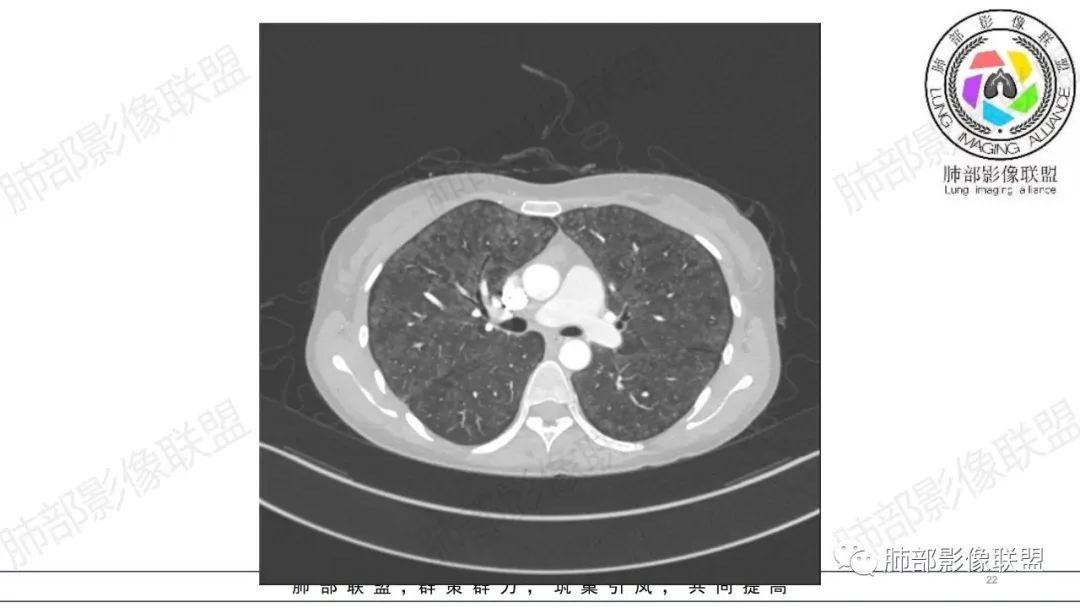

影像资料

34岁女性患者,“哮喘”病史30年,近期有可疑刺激性气体吸入史;因乏力半年,咳嗽、憋气、发热4天就诊;6.1CT提示双肺广泛毛玻璃影及粟粒样结节,胸膜下闲置及血管周闲置,可见树丫征,部分小叶间隔增厚。考虑:1.过敏性肺泡炎,有可疑刺激气体接触史,胸膜下闲置,广泛毛玻璃影,地图样分布,粟粒结节边界模糊,支持过敏性肺泡炎,但糖皮激素治疗效果不佳,且动态复查血常规血红蛋白进行性降低,过敏性肺泡炎 不符合;2.肺含铁血黄素沉积症:患者30“哮喘”病史,可能为肺含铁症状,肺部CT提示双肺弥漫毛玻璃影及粟粒结节影,中下肺明显,肺底部分小叶间隔增厚,近期咳嗽、憋气、发热,血常规血红蛋白进行性下降,考虑肺含铁急性期症状,但临床无咯血症状,肺含铁不典型。综合考虑:肺含铁血黄素沉积症>过敏性肺泡炎。

年轻女性 ,急性喘息发热,肺部影像弥漫磨玻璃密度,部分细小腺泡结节,胸膜下黑线显示,短期复查,病变密度增高,下肺明显,血管周围肺组织累及较少、且逐渐成小叶间隔分布。考虑弥漫肺泡内病变,并经淋巴道转移,下肺比上肺明显,多为免疫细胞功能下肺较强。1.过敏性肺泡炎,有相关病史,三层密度特点、头尾测分布,符合。2 肺泡微石症,多有钙化,且缓慢起病,病程不太符合,放待排。3 吸入相关肺损伤,有病史,疾病演变过程也符合渗出-肉芽肿改变,建议详细询问病史。4 感染性病变,结核?病变气道分布为主,如此弥漫且没有树丫不符合。5.巨细胞病毒,可以磨玻璃 结节 改变,没有免疫缺陷病史。最后考虑吸入所致 1过敏性肺泡炎、吸入性肺损伤 鉴别肺泡微石症。

肺内气腔磨玻璃结节,肝脾肿大,治疗后间质改变,弥漫大B可能